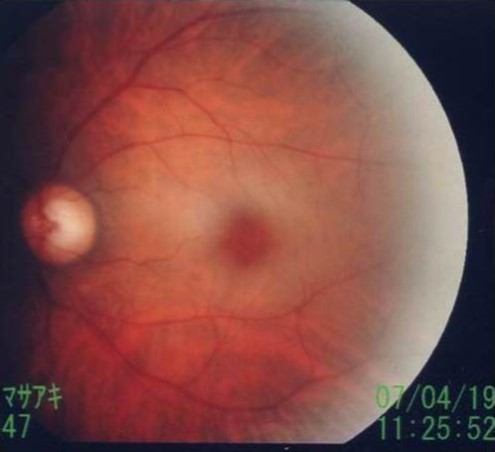

The following day (April 19, 2007), the corrected visual acuity of the left eye was 1.2; funduscopy showed a cherry red spot, characteristic of CRAO (Figure 4). Vision in the left eye subsequently improved gradually. At hospital discharge, although not perfect, vision had improved to the point where no impairment to daily activities was present.

Figure 4.Cherry red spot. Funduscopy showed a cherry red spot.

During the acute phase, within a few hours after onset, the retina appears normal, with characteristic findings developing within 24 h. The posterior pole of the retina is edematous and opaque, the retina thins at the fovea, and red coloration of the choroid is visible as a “cherry red spot” on funduscopy (Figure 4)8.